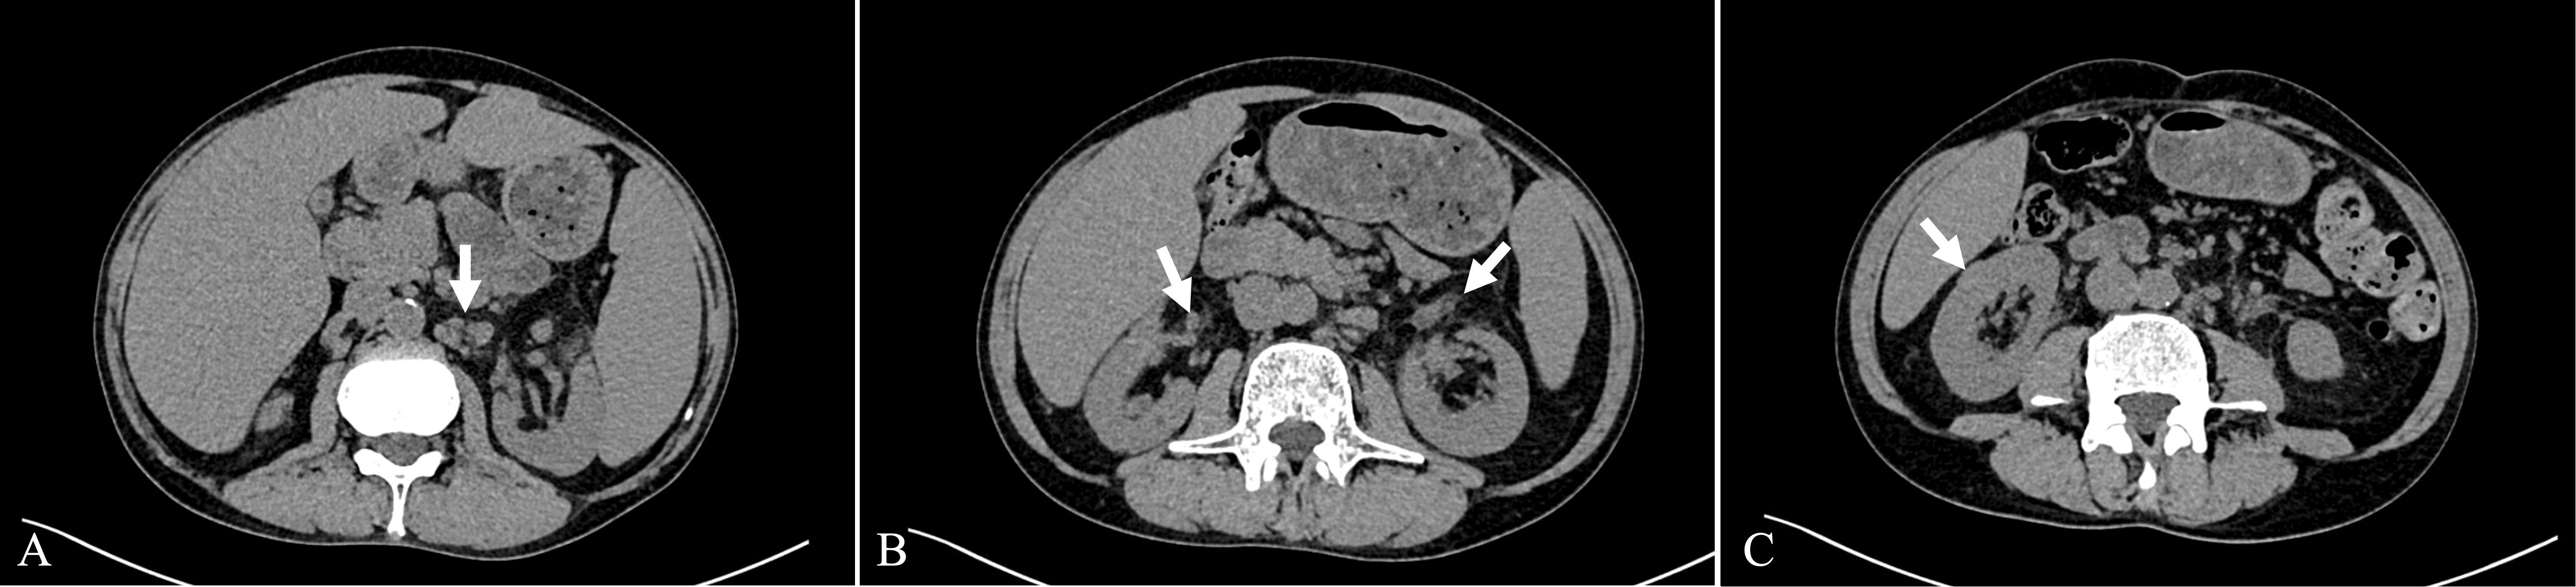

Immunoglobulin G4-related disease (IgG4-RD) is a systemic immune-mediated fibroinflammatory condition affecting multiple organs. IgG4-related tubulointerstitial nephritis (IgG4-TIN) is the predominant pattern of kidney involvement. Amyloid A (AA) amyloidosis is a systemic amyloidosis that develops secondary to chronic inflammation or infection, most frequently affecting the kidneys. The association between IgG4-RD and AA amyloidosis is rarely reported. Herein, we report a case of a 56-year-old Chinese man presenting with a one-year history of dizziness and fatigue. The clinical evaluation and laboratory findings showed multiple enlarged lymph nodes, elevated serum creatinine, and increased levels of IgG4 and C-reactive protein. A kidney biopsy revealed IgG4-TIN. Furthermore, patchy congophilic amyloid deposits in the interstitium and arteriolar walls were positive for AA protein by immunohistochemical staining. Subsequent cervical lymph node biopsy showed IgG4-related lymphadenopathy. With prednisone and cyclophosphamide treatment, the patient achieved complete remission of renal function and a noticeable decrease in IgG4 and C-reactive protein levels. This is the first reported case to our knowledge of IgG4-related lymphadenopathy, IgG4-TIN, concurrent with renal AA amyloidosis. Clinicians should be aware that AA amyloidosis may occur in patients with IgG4-TIN, warranting further investigation into the underlying mechanisms linking AA amyloidosis to IgG4-RD.